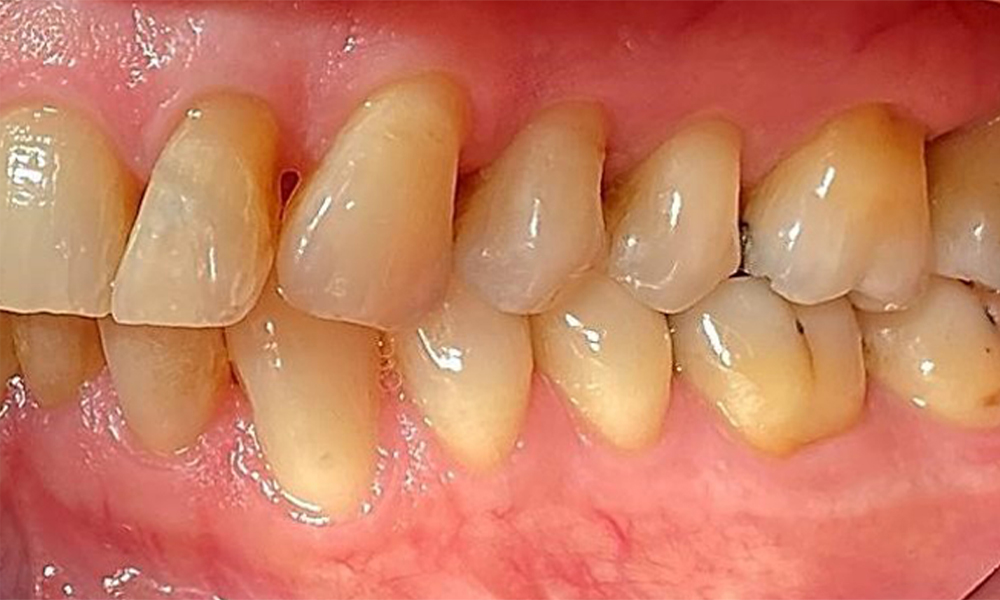

Десен страничен изглед. Загуба на интерденталните папили.

Фиг. 3 Десен страничен изглед. Загуба на интерденталните папили. © д-р Р. Крапф

Изглед от лявата страна, включващ рецесиите.

Фиг. 4 Изглед от лявата страна, включващ рецесиите. © д-р Р. Крапф

Пациентът е с пародонтит II стадий, степен В (5). Клиничните дълбочини на сондиране от 1 до 3 mm са във физиологичния диапазон. Локализирани дълбочини на сондиране от 5 mm са наблюдавани медиопалатинално на 17 и 27. Налице са генерализирани рецесии от 1 до 3 mm с частична загуба на интердентални папили (фиг. 2, фиг. 3, фиг. 4)